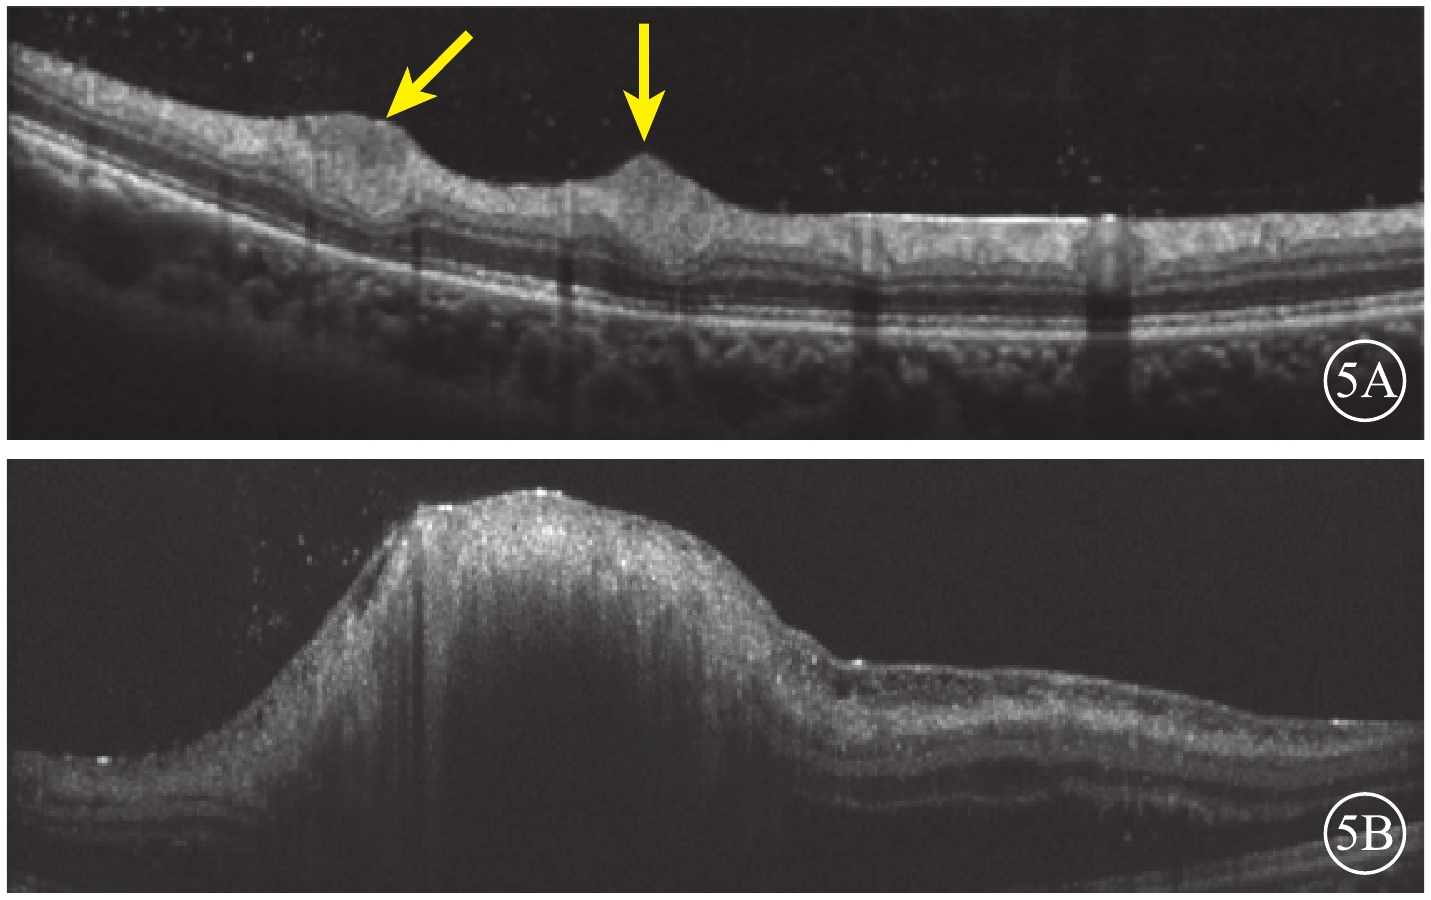

患者男,27歲。因視力下降1周來我院就診。既往有癲癇病史,目前藥物控制。右腎腫瘤切除手術后1年余,病理檢查結果提示錯構瘤。顱腦CT檢查,雙側側腦室旁、右側小腦半球多發鈣化,左側側腦室前角占位性病變。顏面部多個血管纖維瘤及耳后纖維斑塊(圖1)。雙側多根指甲根部纖維瘤。

圖1

患者皮膚病損圖。1A. 面部纖維血管瘤(黃框);1B.耳后纖維斑塊(黃框)

圖1

患者皮膚病損圖。1A. 面部纖維血管瘤(黃框);1B.耳后纖維斑塊(黃框)

患者男,27歲。因視力下降1周來我院就診。既往有癲癇病史,目前藥物控制。右腎腫瘤切除手術后1年余,病理檢查結果提示錯構瘤。顱腦CT檢查,雙側側腦室旁、右側小腦半球多發鈣化,左側側腦室前角占位性病變。顏面部多個血管纖維瘤及耳后纖維斑塊(圖1)。雙側多根指甲根部纖維瘤。

圖1

患者皮膚病損圖。1A. 面部纖維血管瘤(黃框);1B.耳后纖維斑塊(黃框)

圖1

患者皮膚病損圖。1A. 面部纖維血管瘤(黃框);1B.耳后纖維斑塊(黃框)